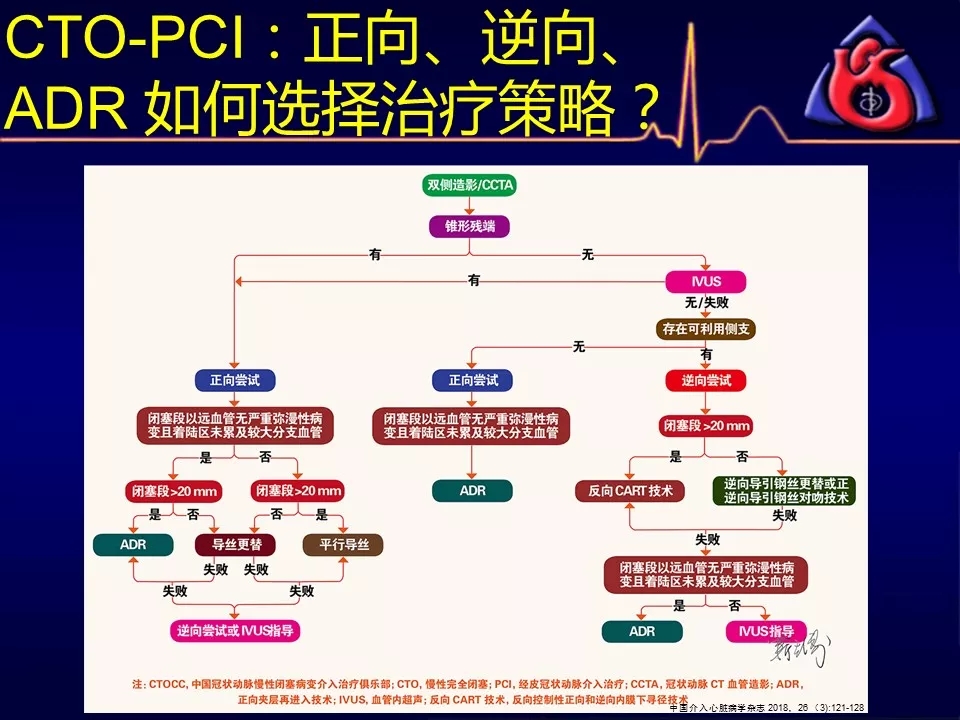

如何选择正向、逆向、IVUS指引及ADR技术?